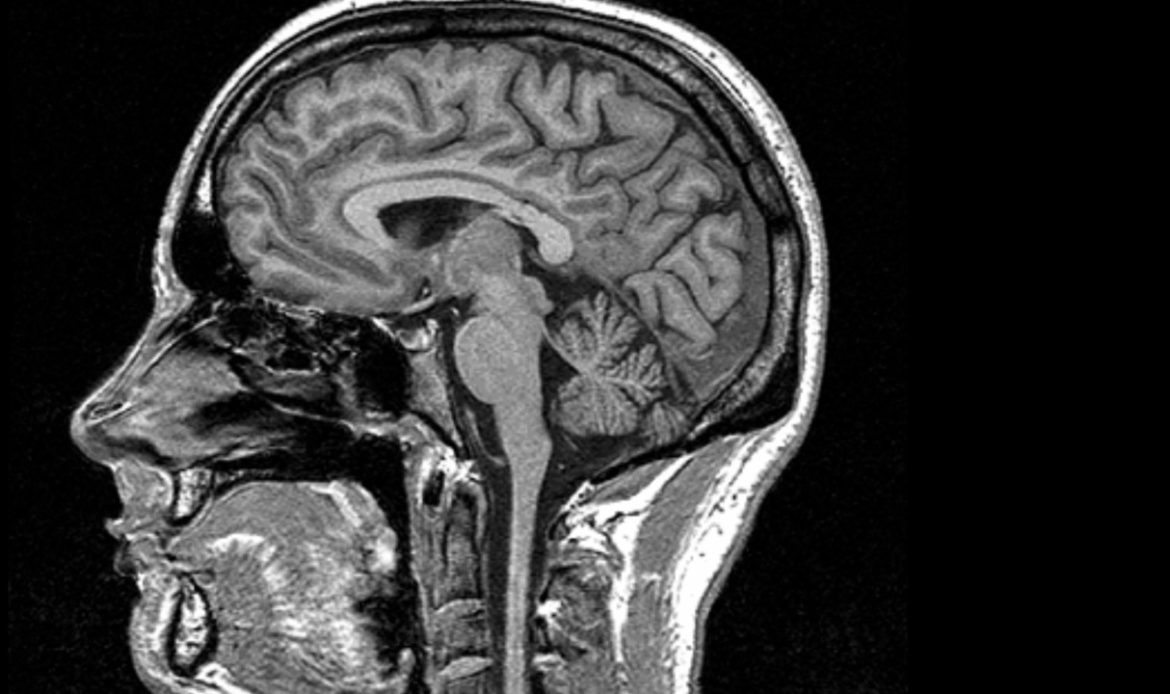

Группа американских исследователей провела эксперимент, чтобы выяснить, способны ли регулярные аэробные нагрузки замедлить старение мозга или даже обратить этот процесс вспять. Для оценки состояния органа использовалась магнитно-резонансная томография, результаты которой сопоставлялись с реальным возрастом испытуемых. Итоги работы, опубликованные в научном журнале Journal of Sport and Health Science подтвердили, что физическая активность оказывает положительное влияние на состояние центральной нервной системы. Как показали более ранние научные труды, разрыв между биологическим возрастом мозга и паспортным возрастом человека часто связан с ухудшением когнитивных способностей и повышенным риском преждевременной смерти. Новое исследование продемонстривало, что даже простая программа тренировок способна заметно улучшить показатели всего за 12 месяцев. В эксперименте приняли участие 130 здоровых добровольцев в возрасте от 26 до 58 лет. Участников разделили на две группы: одна занималась аэр

Исследование с помощью МРТ доказало пользу спорта для замедления старения мозга